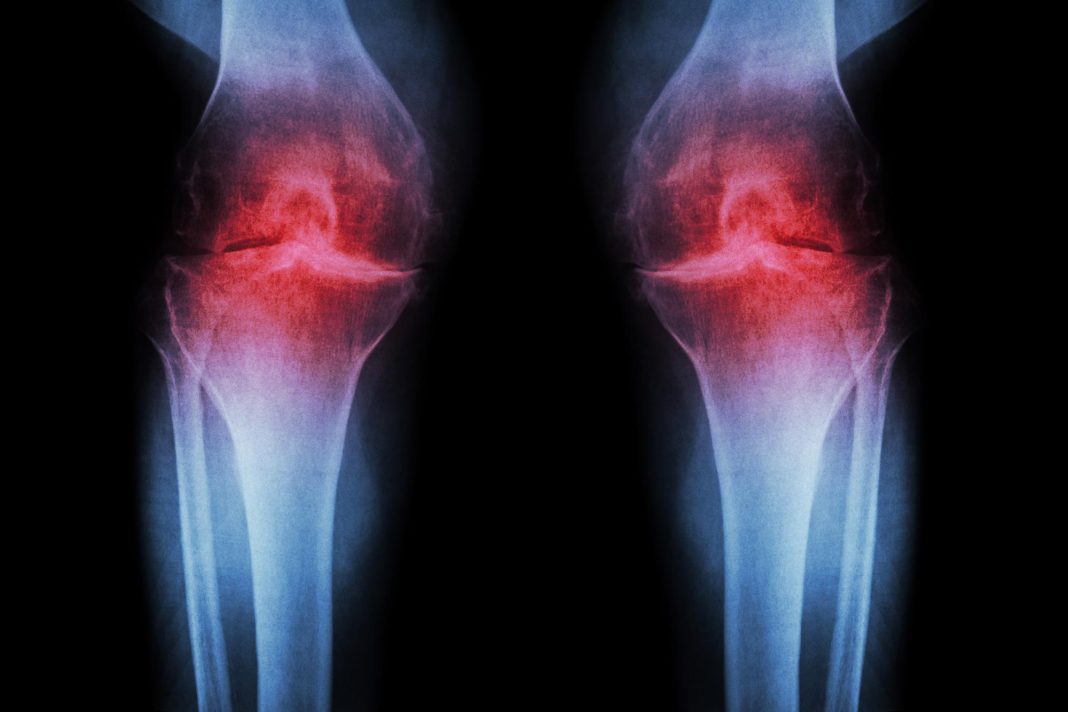

Μια μεγάλη μελέτη διάρκειας επτά ετών αποκαλύπτει ότι η ρευματοειδής αρθρίτιδα (ΡΑ) δεν εμφανίζεται ξαφνικά τη στιγμή που αρχίζουν οι πόνοι στις αρθρώσεις.